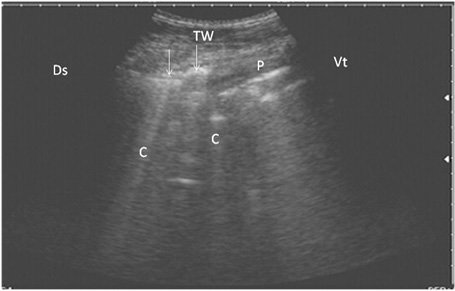

Ultrasonography of bronchopneumonia in cows using a 3.5 MHz transducer. The image shows small hypoechoic circular zones at the lung surface with a comet-tail artifact (white arrows, C), pleura (P) and the thoracic wall (TW). The right part of the image is ventral (Vt) and the left is dorsal (Ds).